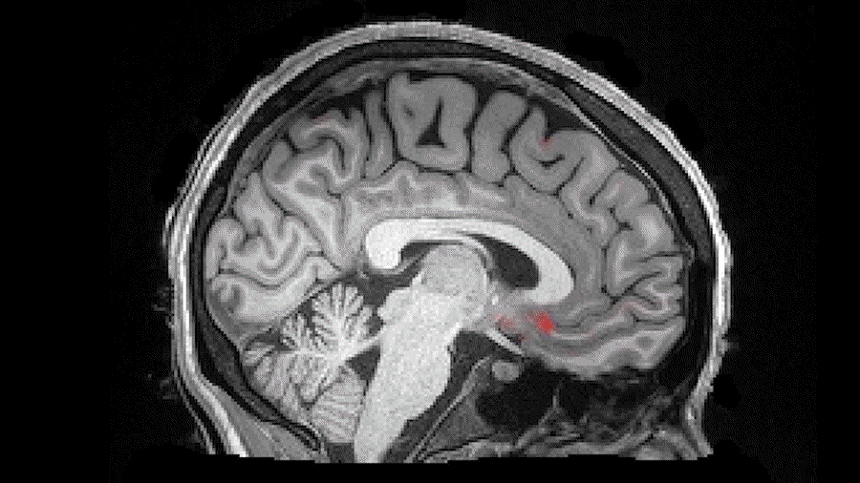

Scientists at Boston University have discovered that during sleep, the brain exhibits waves of blood oxygenation (red) followed by waves of cerebrospinal fluid (blue). Video courtesy of Laura Lewis

New research from Boston University suggests that tonight while you sleep, something amazing will happen within your brain. Your neurons will go quiet. A few seconds later, blood will flow out of your head. Then, a watery liquid called cerebrospinal fluid (CSF) will flow in, washing through your brain in rhythmic, pulsing waves.

오늘밤 당신이 잠자는 동안 무언가 놀라운 일이 당신 뇌속에서 발생한다는 것을 보스턴 대학의 새로운 연구가 제시한다. 당신의 신경세포는 조용해지고 몇초 후 혈액이 당신 머리에서 흘러나오고 그리고 나서 뇌척수액(CSF)이라 부르는 물같은 액체가 흘러 들어가 뇌파에 맞춰 규칙적 순환을 하면서 당신 뇌를 통과해서 세척을 한다.

The study, published on October 31 in Science, is the first to illustrate that the brain’s CSF pulses during sleep, and that these motions are closely tied with brain wave activity and blood flow.

10월 31일 사이언스지에 게재된 그 연구는 뇌척수액이 잠자는 동안 맥박치는 것을 설명한 최초의 것이다. 그리고 이런 운동은 뇌파 활동과 혈류와 밀접하게 연관이 되어있다.